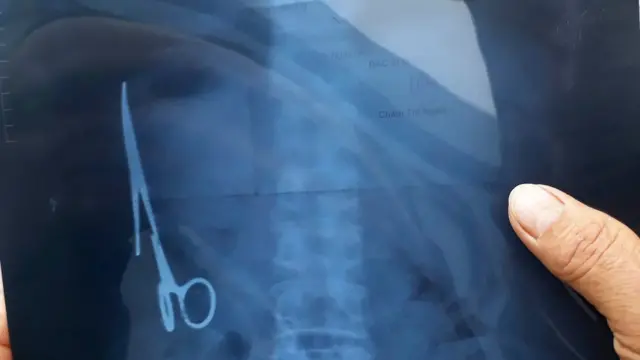

قیچی جراحی هجده سال در شکم بیمار جا مانده بود

یک قیچی جراحی پس از هجده سال از شکم یک مرد ویتنامی خارج شده است.

اخیرا وی به خاطر درد شکم به پزشک مراجعه کرد و سونوگرافی از شکم او وجود یک قیچی پانزده سانتیمتری در نزدیک راست روده (کلون) را نشان داد. این قیچی در جراحی قبلی در جایی در شکم او جا مانده بود.

دو روز پیش، پزشکان بیمارستان تایی تگوین این قیچی را با عمل جراحی خارج کردند و پزشکان معالج او گفتهاند که حال بیمار رضایتبخش است.